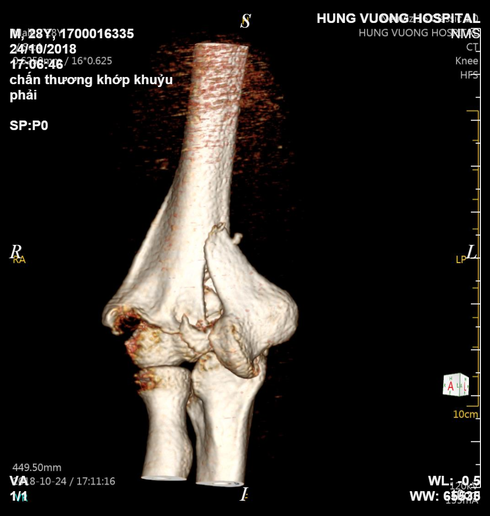

Hình ảnh chụp xương bệnh nhân T |

Còn trường hợp bệnh nhân B.Đ.T, 28 tuổi, cũng ở Đoan Hùng – Phú Thọ vào viện cấp cứu trong tình trạng đau nhiều, biến dạng, mất vận động khuỷu tay phải.

Kết quả chụp CT cánh tay cho thấy hình ảnh vỡ nhiều mảnh kèm di lệch xương lồi trong và ngoài cầu xương cánh tay phải. Sau khi bác sỹ giải thích tình trạng chấn thương của bệnh nhân cho người nhà, bệnh nhân được thực hiện phẫu thuật kết hợp xương trên, liên lồi cầu cánh tay.

Bệnh nhân cho biết do bị trượt chân ngã khi đang đi bộ nên đã lấy tay phải chống xuống đất, sau cú ngã thì không thể cử động tay phải, đau nhiều, nên người nhà đã đưa bệnh nhân đến bệnh viện cấp cứu.

Gãy trên, liên lồi cầu cánh tay là 1 loại gãy khó, vị trí gãy là nơi có hố mỏm khuỷu và hố mỏm vẹt làm xương mỏng và yếu, ổ gãy nội khớp, gần thần kinh quay và thần kinh trụ. Phẫu thuật đòi hỏi tuyệt đối chính xác nếu phẫu thuật viên không có kinh nghiệm xử lý thì rất dễ xảy ra biến chứng ảnh hưởng thần kinh trụ.

Bác sỹ trực tiếp phẫu thuật cho bệnh nhân chia sẻ: Chấn thương của bệnh nhân T. khá nghiêm trọng, lồi cầu vỡ thành nhiều mảnh nhỏ nên khi phẫu thuật các bác sỹ cần phối hợp ăn ý và chính xác. Bệnh nhân đã được đặt lại lồi cầu, kết hợp xương và nẹp vít 2 cột trụ, cố định mỏm khuỷu.

Hiện tại sau phẫu thuật bệnh nhân đang được theo dõi tại khoa Ngoại bệnh viện. Bệnh nhân trong độ tuổi có chất lượng xương tốt, khả năng phục hồi nhanh nhưng cần tập phục hồi chức năng tích cực sau khi đã ổn định vết mổ.